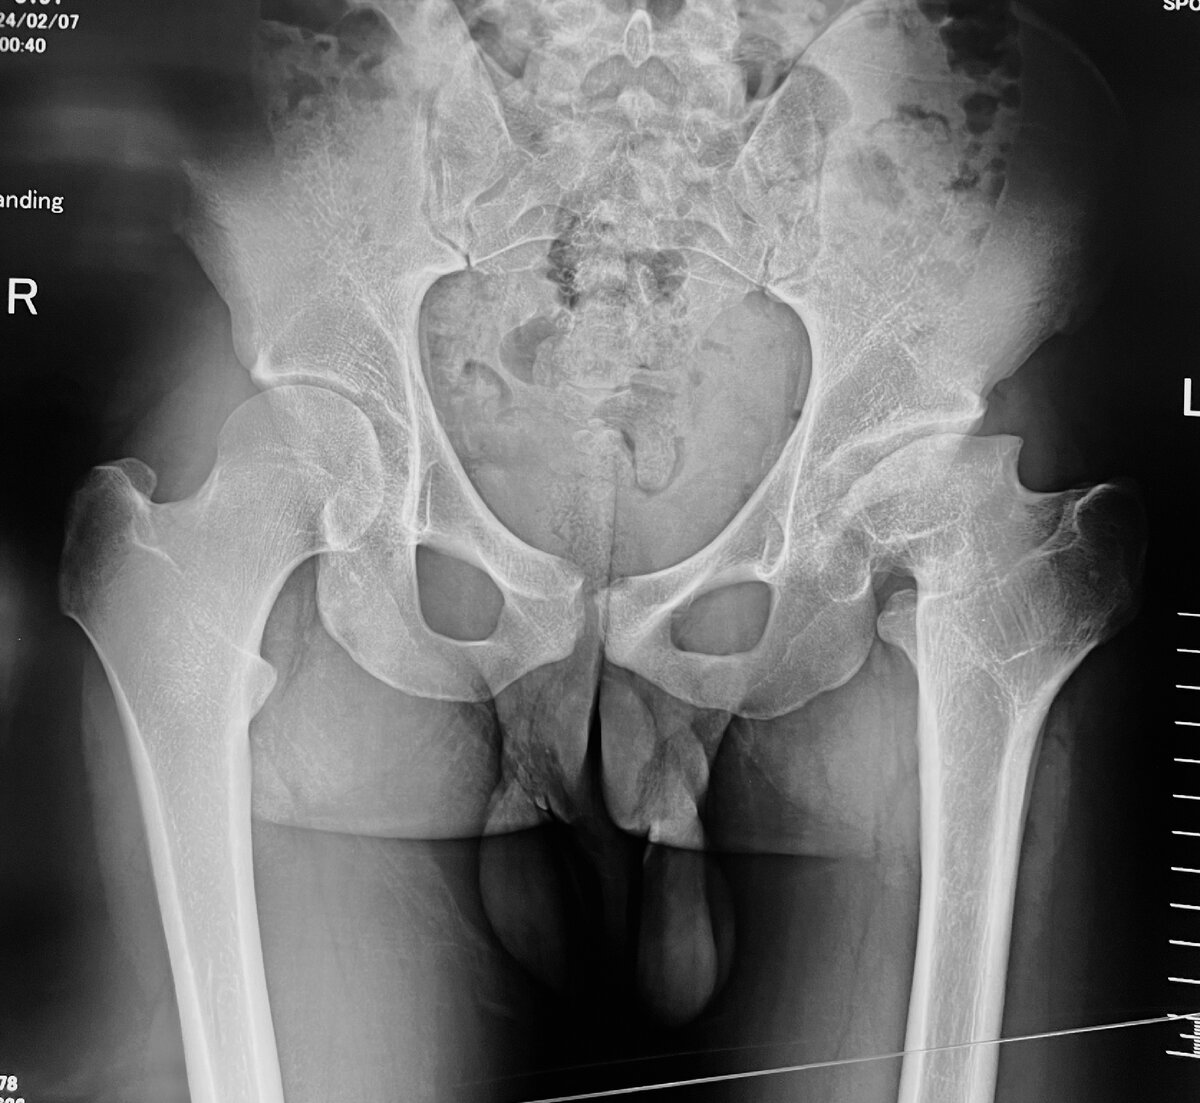

Вот такая картина была еще вчера утром